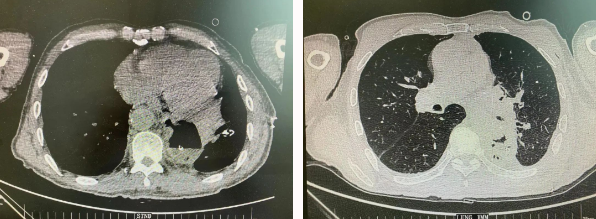

近日,胸科醫(yī)院執(zhí)行院長李小飛教授帶領(lǐng)胸外科一病區(qū)團(tuán)隊(duì)完成一臺(tái)復(fù)雜胸外科手術(shù):食管癌與肺癌同期手術(shù)。

患者王某不幸同時(shí)患食管癌與左肺癌,病理類型系雙源發(fā)腫瘤,食管為鱗癌、肺為腺癌。食管癌和肺癌為胸外科最常見的疾病,但同時(shí)患兩種疾病,十分罕見。家屬輾轉(zhuǎn)多個(gè)醫(yī)院,得知李小飛院長擅長胸外科復(fù)雜手術(shù),慕名來西安國際醫(yī)學(xué)中心醫(yī)院。

經(jīng)過李小飛教授、李文海副教授、穆強(qiáng)副主任醫(yī)師團(tuán)隊(duì)積極準(zhǔn)備,排除手術(shù)禁忌;經(jīng)過全科術(shù)前充分討論,大家認(rèn)為:如果分兩次進(jìn)行手術(shù),另一種疾病勢(shì)必會(huì)受到影響,腫瘤可能進(jìn)展。胸外科手術(shù)對(duì)呼吸循環(huán)影響較大,同期實(shí)施兩個(gè)手術(shù)更要小心謹(jǐn)慎。李小飛教授主持術(shù)前討論,設(shè)計(jì)合理手術(shù)方式,由于食管癌胸腔鏡手術(shù)為右側(cè)入路,但為兼顧左肺癌手術(shù),則采用傳統(tǒng)左開胸手術(shù)。

2022年4月25日,由李小飛教授主刀,同期行左側(cè)開胸:食管癌根治術(shù) 左肺癌根治術(shù),一次手術(shù)同時(shí)根治兩種惡性腫瘤疾病。經(jīng)過精細(xì)手術(shù)及術(shù)后管理,患者術(shù)后十天,恢復(fù)良好,進(jìn)食良好,現(xiàn)已出院。